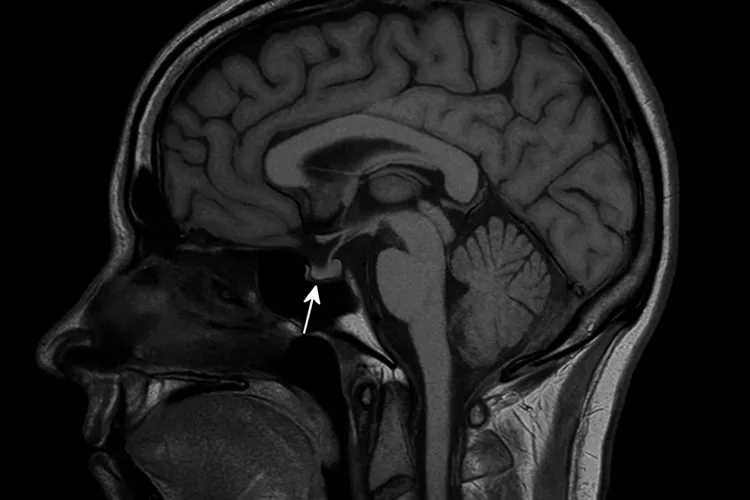

Большинство образований внутри черепной коробки связано с аденомой гипофиза. Некоторые из них могут возникать в зоне Турецкого седла, поэтому…